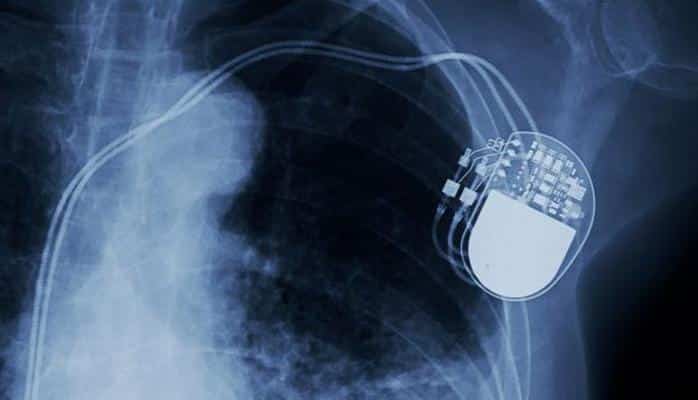

Ürək xəstəliyindən əziyyət çəkən pasiyentlərin müalicəsi üçün nəbzlərində ciddi pozuntu olanlara defibrilyatorlar implantasiya edilir.

Təcili yardım xidmətlərində istifadə olunan defibrilyatorlardan fərqli olaraq xəstəyə implantasiya edilən defibrilyator kiçik ölçülüdür və xəstənin dərisinin altına implantasiya olunur.

Defbrilyator ürək ritmini izləməyə imkan verir.

Nəbzin pozulması halları elektrik impulslar vasitəsiylə müalicə olunur.

Bu cür cihazların ilk versiyası 1980-ci illərdə ilk dəfə sınaqdan keçirilib.